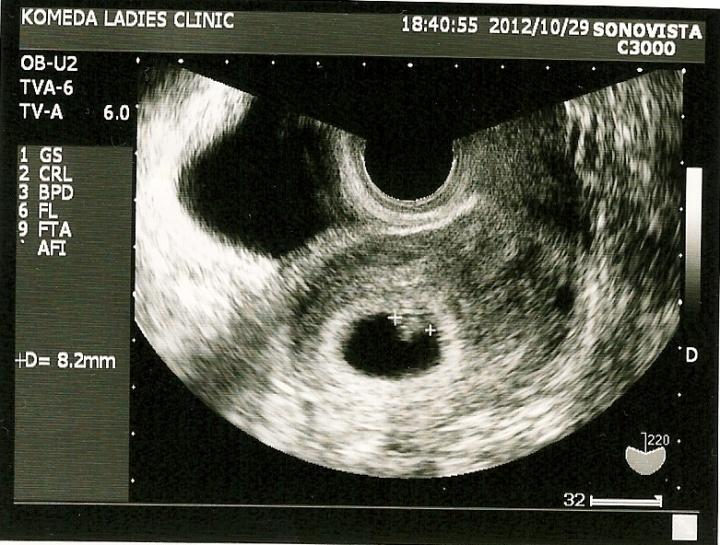

7週目突入(^^)